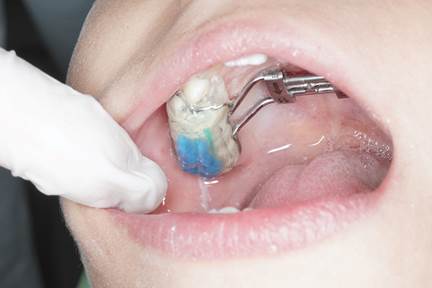

Durante el tratamiento (vista lateral): Detalle de la pista directa incorporada sobre el disyuntor, diseñada para favorecer la masticación bilateral alternada y corregir la desviación mandibular.